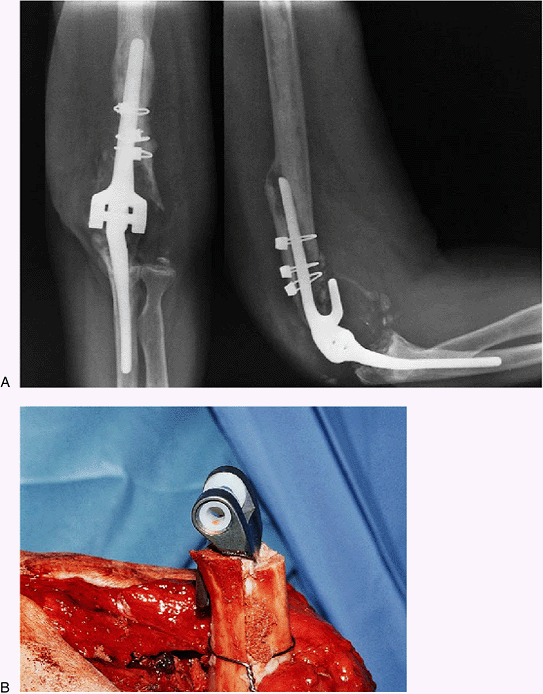

ulnar component 3 years after a custom implant was inserted, at which

time the ulna was fractured. This device had a rigid hinge with no

laxity or freedom at the articulation. The radiograph demonstrated

loosening of the ulnar component, but the humeral side looked solidly

fixed. Nevertheless the patient had pain with internal and external

rotation of the humerus (Fig. 19-26). At the

time of revision the humeral component was in fact loose, as was the

proximal ulna. A long-flanged humeral component was used (Fig. 19-27).

The ulna fracture had not healed, requiring a long ulnar implant with

strut grafting. Excellent motion from 20 to 135 degrees and minimal

pain were present as found (Fig. 19-28).

Figure 19-27. A long-flanged implant was used.

![]() |

|

Figure 19-28. The long flange and humeral and ulnar strut grafts were used.